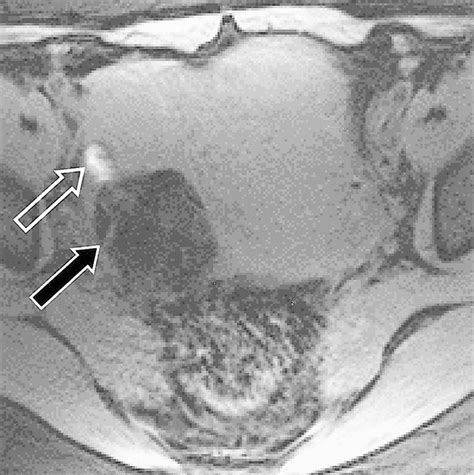

When doctors request scans, they are looking for specific visual identifiers. Imaging techniques such as CT scans, MRIs, and ultrasounds are standard. In these images, a teratoma often appears as a complex mass with both cystic (fluid-filled) and solid components. The presence of fat, calcifications (which look like bone or teeth on an X-ray), and soft tissue elements are hallmark signs that radiologists use to identify the growth.

While looking for Teratoma Cancer Pictures online, patients may see varying representations, but it is important to note that internal clinical imaging (like an MRI) looks significantly different from external surgical photography. Radiology provides the map for surgical intervention, helping surgeons understand the proximity of the tumor to vital organs.